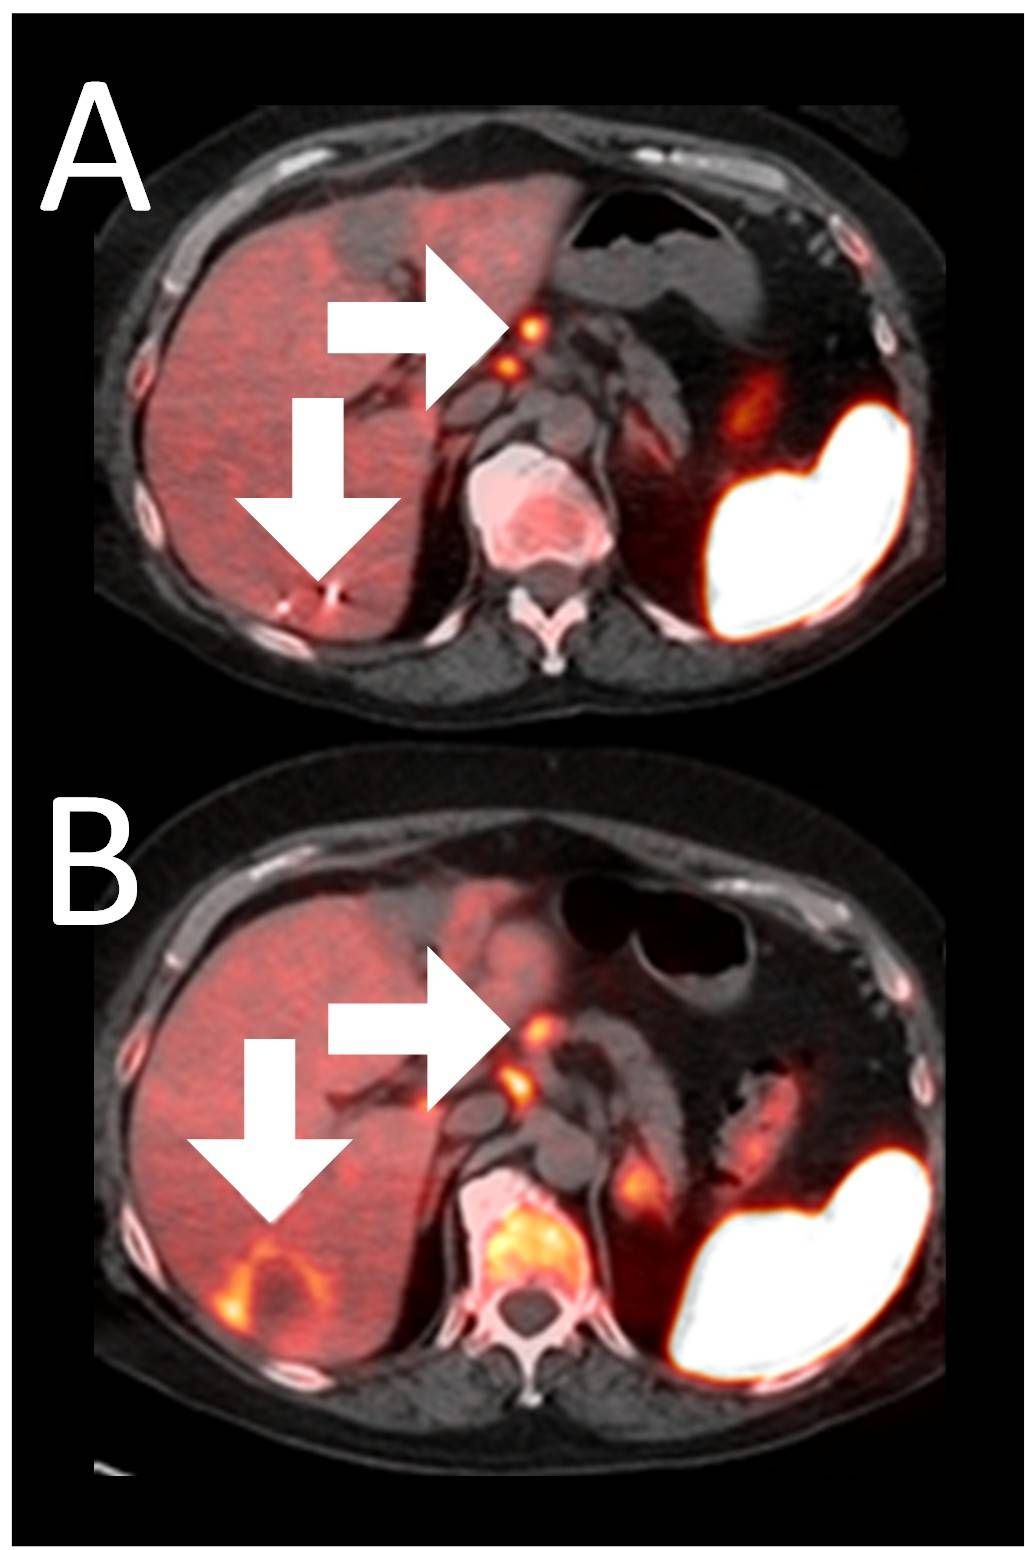

Example 3: Patient 15-006:

A 64-year-old woman with ER+/PR-/HER2- metastatic breast cancer, heavily pre-treated with 8 prior lines of therapy, including the antibody-drug conjugate Trodelvy, remains alive 25 months post-enrollment. At baseline, presented with hepatic metastasis.

Before BriaCell Treatment Image A: A liver metastasis (lower arrow) is "cold," indicating minimal to no CD8+ cytotoxic T cells in the tumor while enlarged lymph nodes (upper arrow) show moderate uptake.

After BriaCell Treatment Image B: Swelling (induration) around the metastasis (lower arrow) demonstrates the liver metastasis has become "hot", indicating marked CD8+ cytotoxic T cell infiltration while further lymph node enlargement is consistent with increased activity (upper arrow) indicating increased CD8+ T cells.

Example 3 Images (Patient 15-006): Combined MRI and CD8 ImmunoPET images Pre (A) and Post (B) Bria-IMT treatment